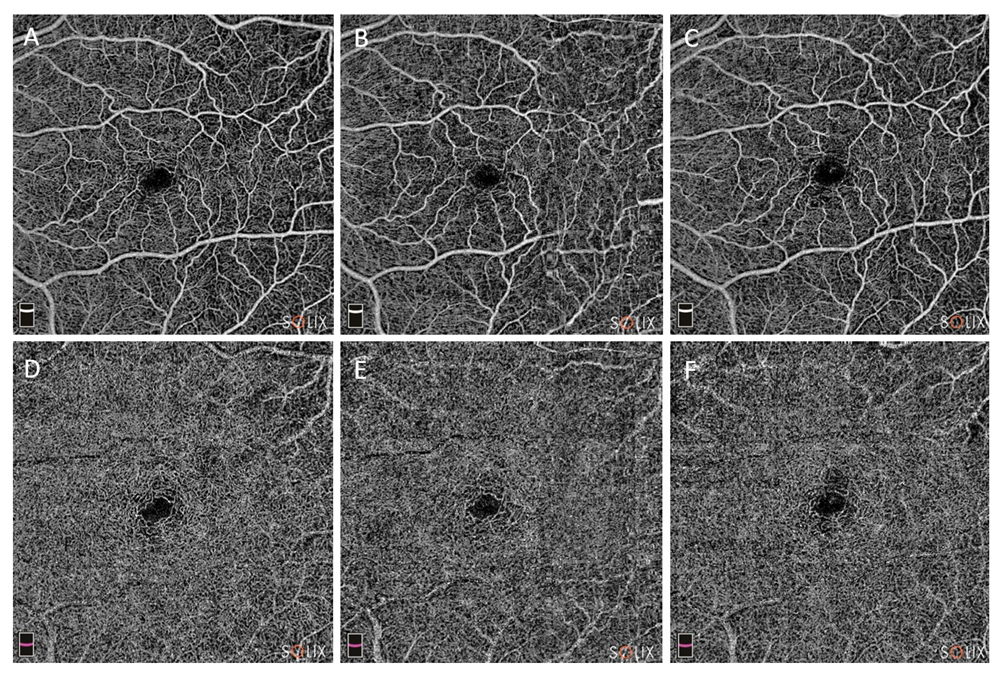

When compared to baseline, there was a significant increase in SCP vessel density at T30 (from 42.9 ± 4.2 to 45.6 ± 5.4, p = 0.0001). On the other side, SCP vessel density at T7 showed a non-significant tendency to increase compared to T0 (43.4 ± 4.6, p = 0.85). Similarly, DCP vessel density at T0 was 37.3 ± 7.4%, at T1 was 37.7 ± 10.4% (p = 0.92), but showed a significant increase at T30 (43.7 ± 9.1%, p = 0.0002) (Figure 1).

Figure 1. AngioVue Retina images of macular vascularization during the follow ups, in 6.4 × 6.4 mm scans. Upper images highlight the superficial capillary plexus (SCP): baseline (A), one week after cataract surgery (B) and one month after surgery (C). At last follow up, a significant increase in both whole image and foveal vascular density were reported (from 48.3% at T0, to 48.4 at T7, to 51.9% at T30). Similarly, the lower images show the deep capillary plexus (DCP) evolution at T0 (D), T7 (E) and T30 (F). DCP vascular density improved from 50.1% at T0, to 49.8% at T7 and finally to 54.0% at T30.